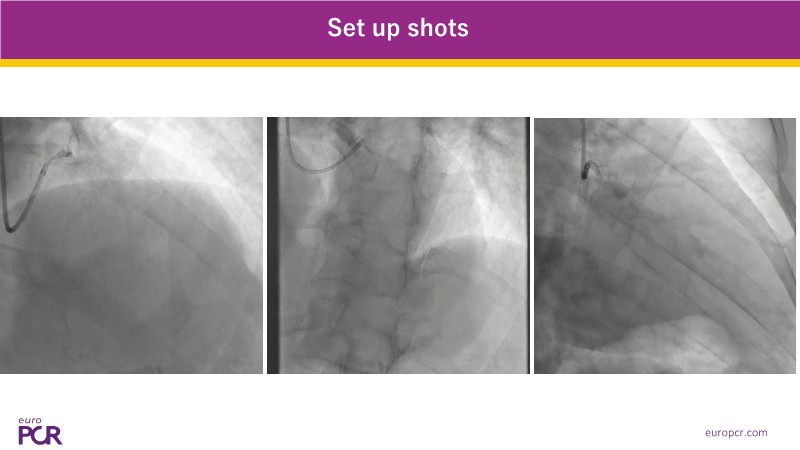

This EuroPCR 2025 session highlights how CathWorks FFRangio is reshaping coronary physiology assessment worldwide. Through case-based experience and real-world data, it showcases the integration of FFRangio into routine clinical workflows—from early adoption at Clinique Pasteur in Toulouse to implementation across the UK. The session also presents the growing body of diagnostic and clinical outcome evidence, along with a look at how FFRangio is evolving toward becoming a new standard of care in the cathlab.

- To explore the practical application of FFRangio in routine practice